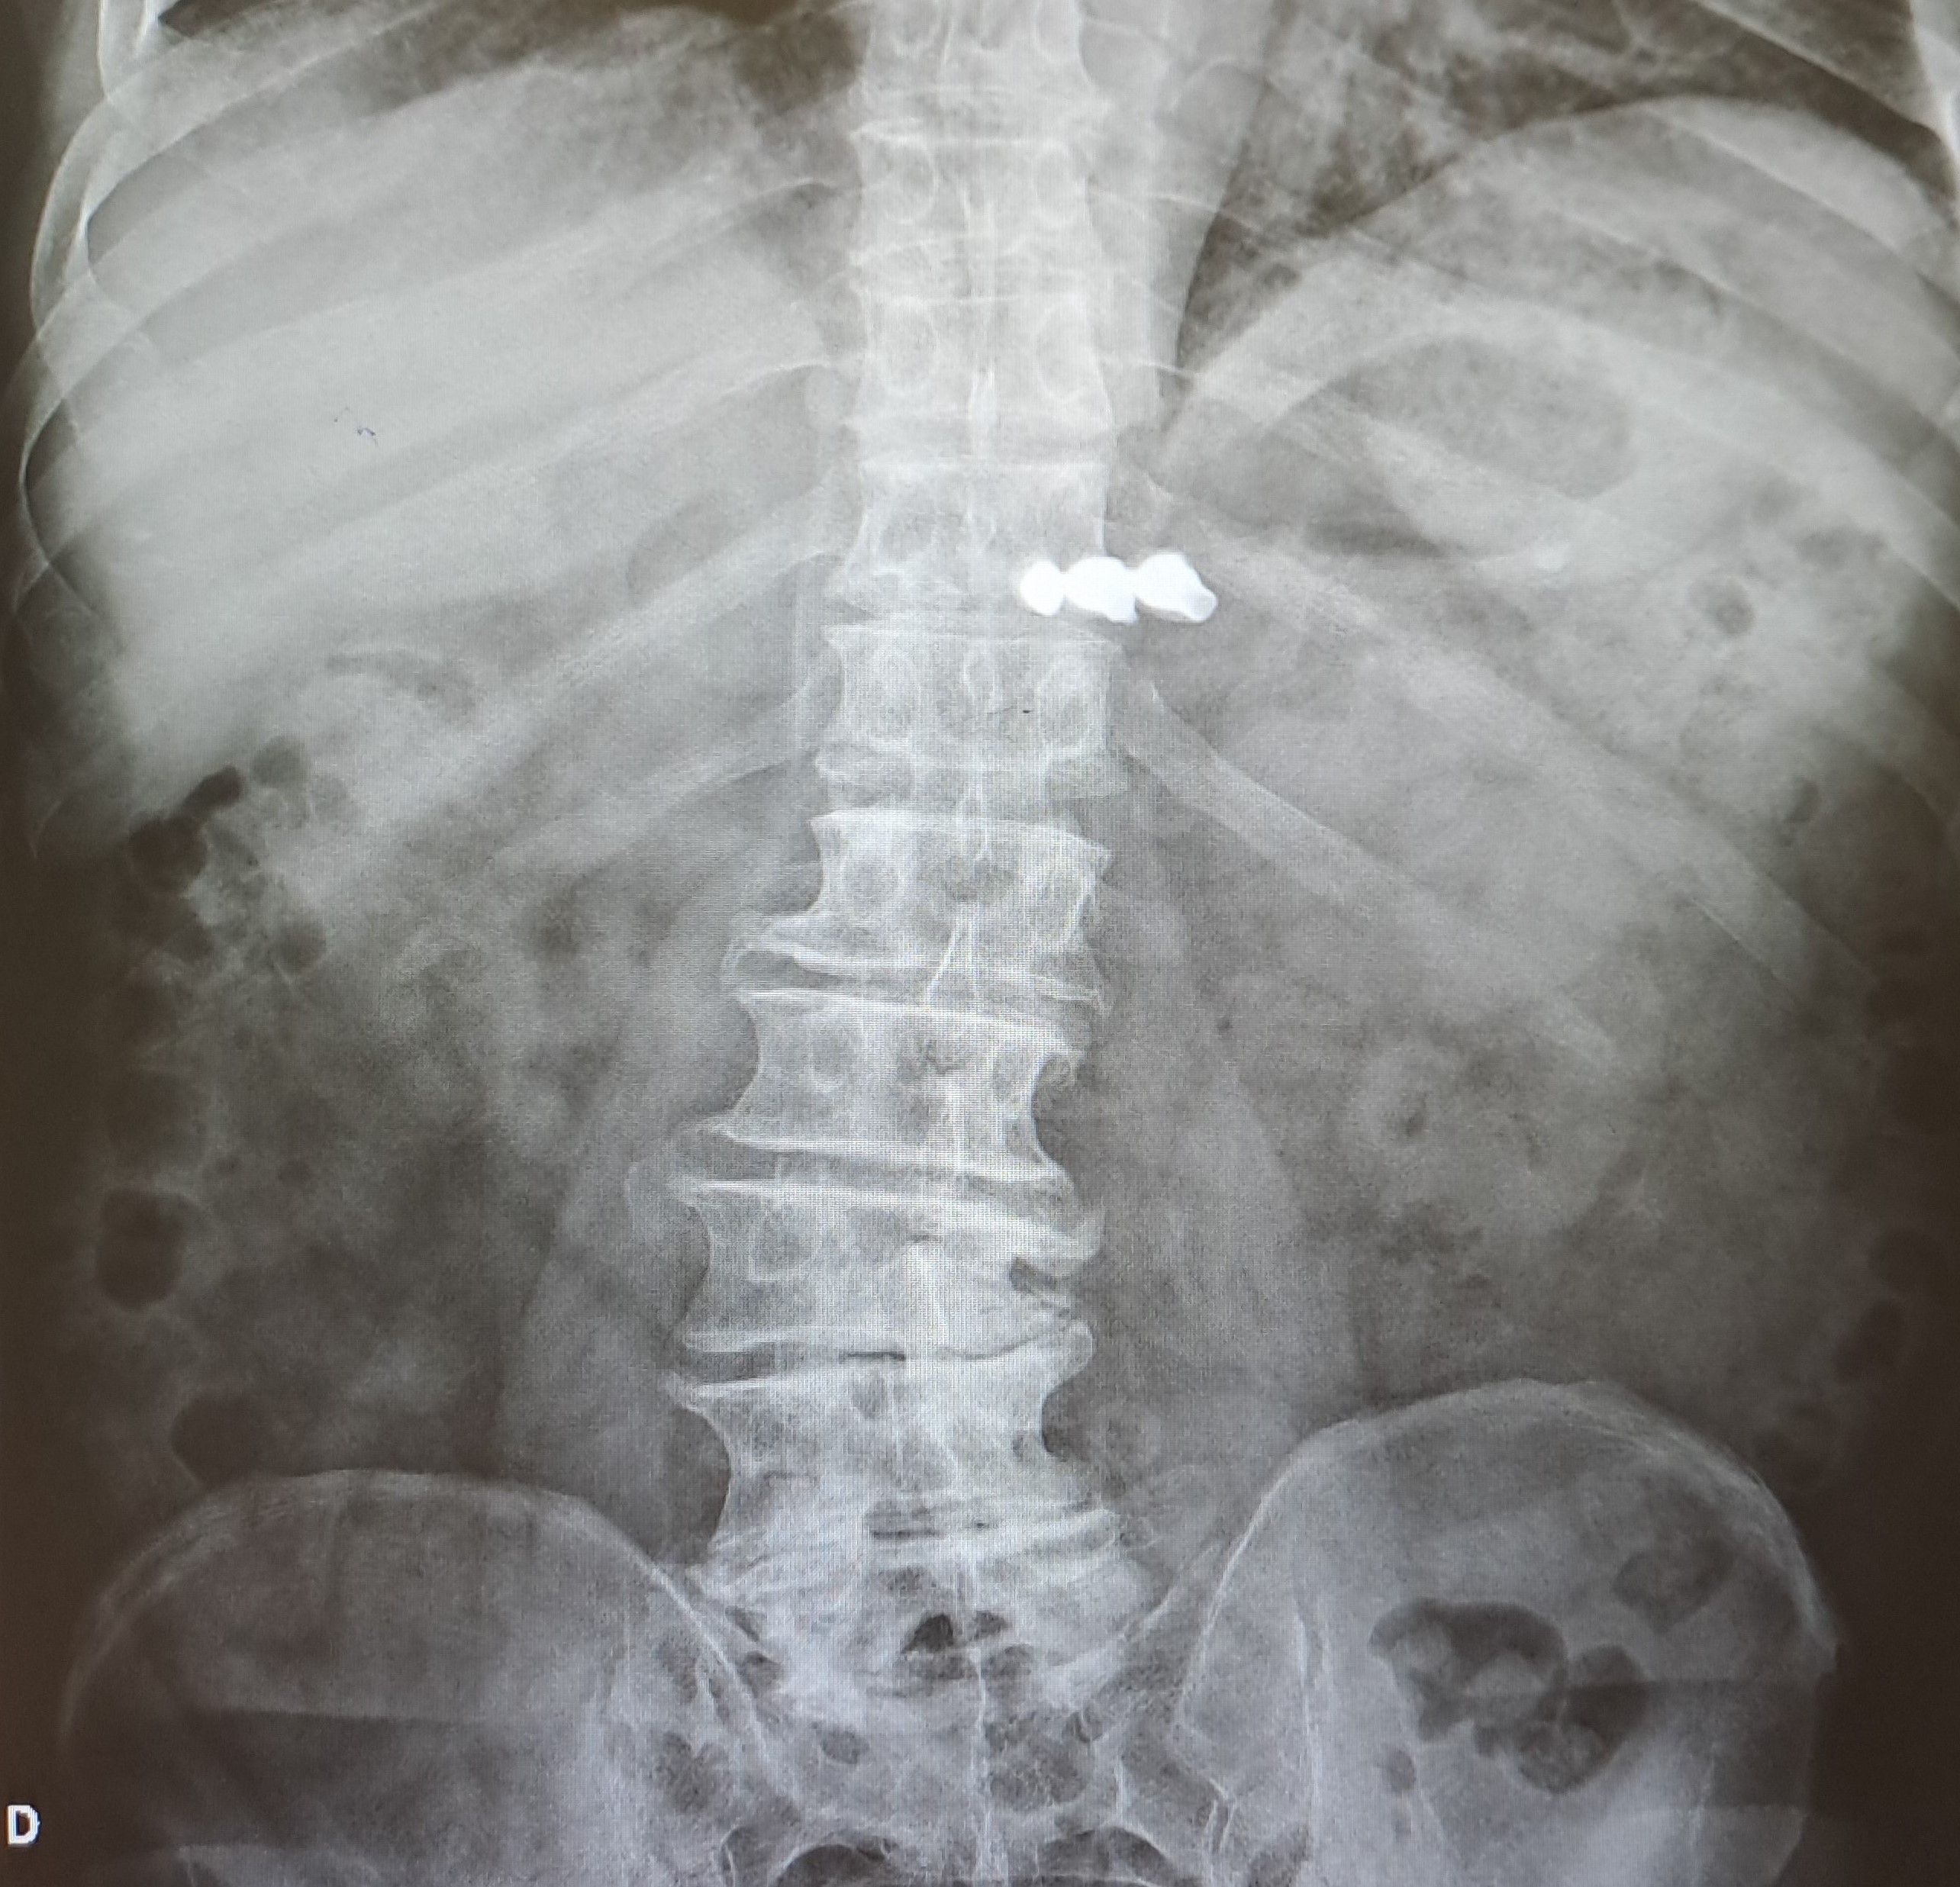

Hombre 63 años, no antecedentes médicos o quirúrgicos de interés. Acude por ingesta de prótesis dental hace 48 horas. Acudió al servicio de urgencias tras la ingesta siendo valorado con radiografías abdominales objetivando cuerpo extraño en hipocondrio izquierdo. Se realizó gastroscopia con sedación sin llegar a objetivar cuerpo extraño en estómago ni en porción proximal del duodeno, por lo que se realizó nueva radiografía abdominal de control al día siguiente objetivando cuerpo extraño en marco cólico derecho. Por lo que fue dado de alta con vigilancia de deposiciones. Refiere ausencia de visualización de la prótesis dental en las últimas deposiciones en el domicilio. Niega dolor abdominal, náuseas o vómito, no fiebre.

Repetimos radiografía sin objetivar cuerpo extraño, aunque no se visualiza ampolla rectal en la radiografía solicitada.